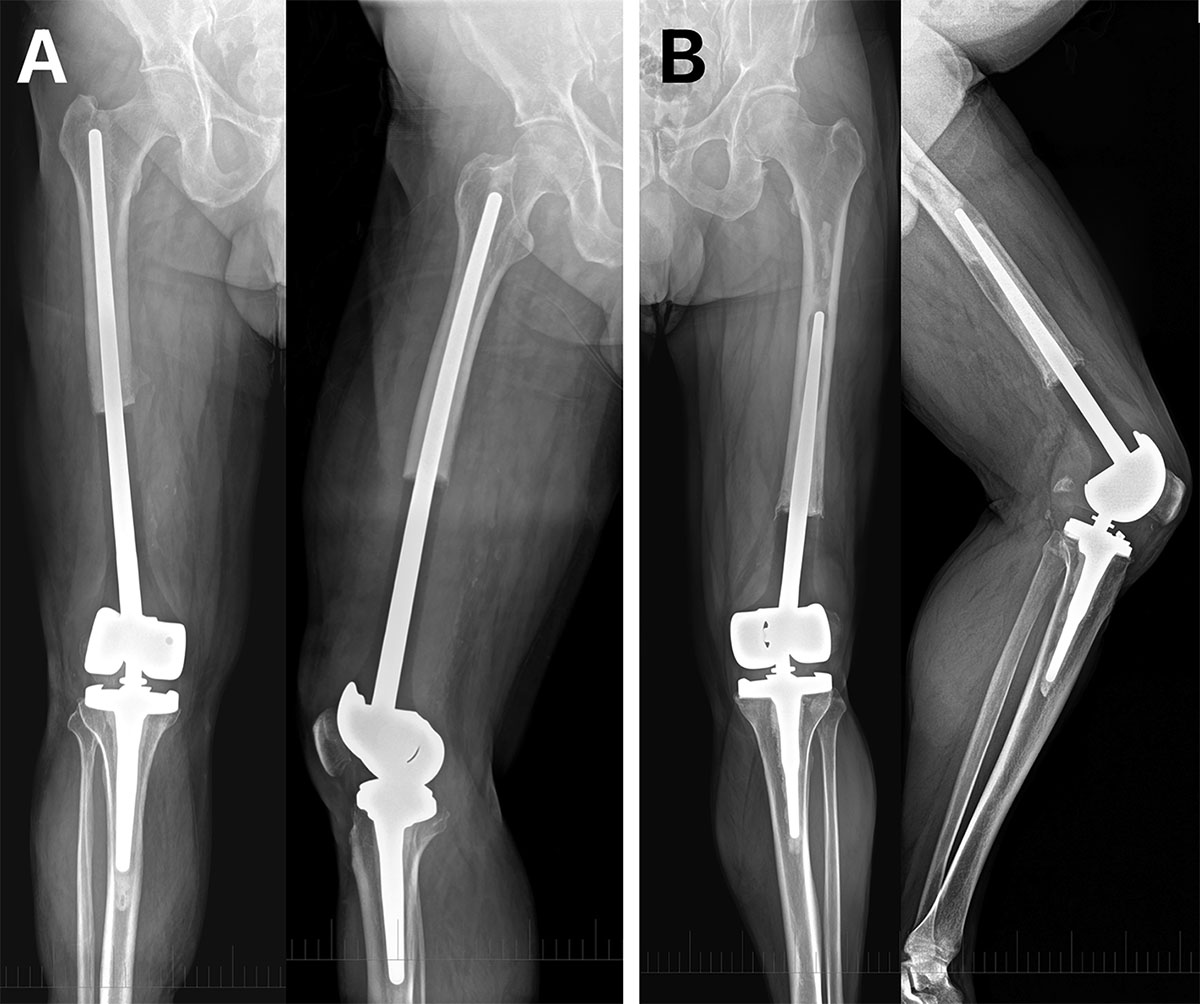

Representative radiographs of cemented custom-made distal femoral megaprosthetic reconstruction after tumor resection. (A) Patient following resection of a conventional grade 2 chondrosarcoma with a 20 cm distal femoral defect reconstructed using a cemented custom-made distal femoral replacement (stem diameter 14 mm, fixation length 21 cm). (B) Patient with malignant epithelioid hemangioendothelioma treated with distal femoral resection of 14 cm and reconstruction using a cemented custom-made megaprosthesis (stem diameter 16 mm, fixation length 17 cm), demonstrating aseptic loosening 6 years after implantation.